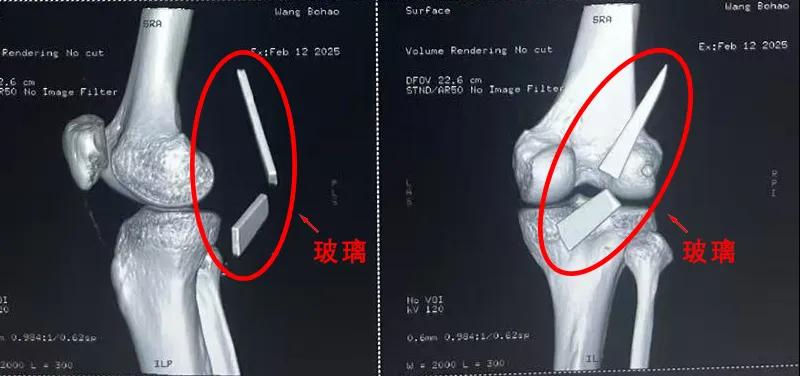

患者家屬這才開始意識(shí)到問題的嚴(yán)重性,便帶著孩子到鄉(xiāng)鎮(zhèn)衛(wèi)生院檢查——結(jié)果顯示右膝關(guān)節(jié)后方竟然殘留著兩塊兒鋒利的碎玻璃,測量后預(yù)估玻璃總長將近13厘米!

由于玻璃位置毗鄰坐骨神經(jīng)和股動(dòng)脈,一旦刺破股動(dòng)脈,將嚴(yán)重威脅生命。家屬著急萬分,想著能否盡快手術(shù)取出碎片,于是慕名來到漯河醫(yī)專二附院(漯河市骨科醫(yī)院、漯河市立醫(yī)院)手顯微外科(修復(fù)重建骨感染科)。

術(shù)中,馬廣輝醫(yī)生憑借扎實(shí)的理論知識(shí)和嫻熟的顯微外科技術(shù),順利找到深深刺進(jìn)肌肉的兩塊玻璃,肉眼可見玻璃尖端距股動(dòng)脈僅有不到半公分的距離!如果患者再耽誤半天或者再多活動(dòng)幾次膝關(guān)節(jié),小指粗的股動(dòng)脈很有可能被玻璃扎破,后果難以想象。